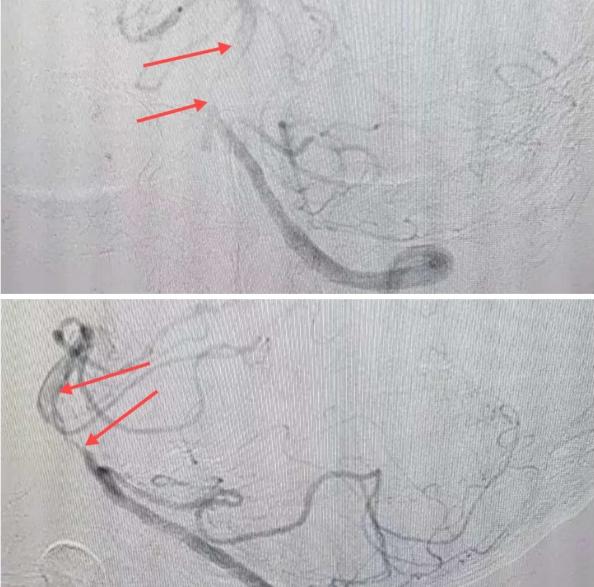

在經(jīng)造影后,主刀醫(yī)生腦一科副主任楊慶堂發(fā)現(xiàn)患者基底動脈下段重度狹窄且狹窄段以遠(yuǎn)有大負(fù)荷血栓,其狹窄處考慮為動脈夾層,手術(shù)難度及風(fēng)險(xiǎn)較大。楊慶堂副主任在彭壯副主任醫(yī)師的協(xié)助下運(yùn)用spaceman(太空人)技術(shù),中間導(dǎo)管抵近血栓抽吸配合支架拉栓,成功開通血管。再次造影可見基底動脈管腔明顯增寬,遠(yuǎn)端血管顯影良好,且等待20分鐘后造影仍顯示血流通暢。楊慶堂副主任考慮到本次手術(shù)時(shí)間不宜過長,現(xiàn)患者基底動脈及分支前向血流維持良好,給予其抗栓藥物應(yīng)用后結(jié)束手術(shù),并建議患者3個(gè)月后復(fù)查造影,明確其基底動脈夾層情況。

造影可見血管夾層和大量血栓形成